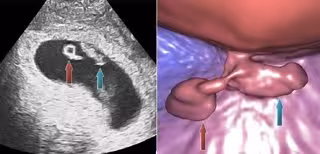

Un equipo de investigadores y médicos de la Universidad de Granada (UGR) y de la Clínica MARGen ha desarrollado una nueva técnica que permite visualizar embriones humanos recién implantados en el útero en realidad virtual, ofreciendo imágenes con una "inusitada nitidez y precisión".

Esta técnica, conocida como embrioscopia virtual y dada a conocer mediante su publicación en la revista británica 'EC Gynaecology', es el método "idóneo" para completar la primera ecografía del embrión recién implantado, tanto en reproducción asistida como en el embarazo espontáneo, y "puede ofrecer información complementaria sobre potenciales riesgos de aborto cuando se utiliza como primera ecografía del embarazo, 4-6 semanas después de la fecundación", según el director del equipo, Jan Tesarik.

Las imágenes generadas por la embrioscopia virtual se muestran en 3 dimensiones y con su color natural, como si el embrión estuviera delante de los ojos del observador. "Aparte de su interés médico, los pacientes están encantados con la calidad de las imágenes y se las llevan a casa como la fotografía del álbum del futuro bebé", ha concluido Tesarik.